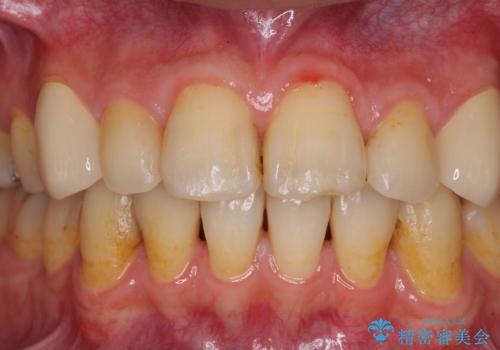

- 以前矯正を行った際に前歯が虫歯だらけとなり、審美面を気にして来院された患者様です。

虫歯の大きかった左右犬歯はオールセラミッククラウンで補綴治療をおこない、4前歯は研磨や古い充填物の詰め直しを行いました。

歯並びは良くなったものの、着色が気になって口元を見せることを躊躇していた用ですが、治療後は他人の視線を気にすることがなくなったようで、大変満足していただきました。